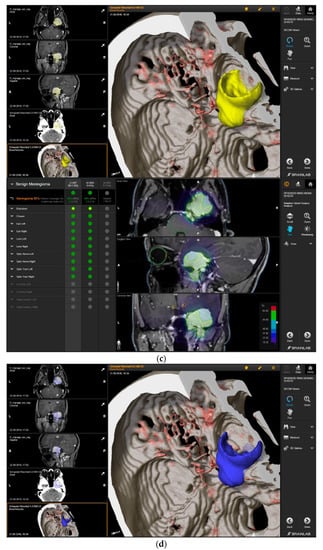

A 58-year-old female presented with progressive headache, difficulty swallowing, diplopia, hearing loss, and reduced face sensitivity on the right side (Figure 4). Elective craniotomy and AHSA-assisted tumor resection were performed. The patient underwent hypofractionated radiosurgery (5 × 5 Gy) of the residual meningioma one year after tumor resection.

Figure 4.

Second representative case of AHSA-supported tumor resection. (a) MRI imaging of petroclival meningioma (axial, coronal, sagittal). (b) Depiction of preoperative tumor volume (orange) and planned residual tumor volume (red). (c) AHSA summary table showing the stereotactic radiation constraints for the preoperatively planned residual tumor volume. With this plan, conventional fractionation and hypofractionation were feasible with effective tumor coverage.

—brainstem: mean dose is safe, while the max. dose is marginally safe;

—right optic tract: mean dose unsafe, max. dose is marginally safe;

—right hippocampus: marginally safe, and mean dose unsafe, max. dose is marginally safe. (d) First intraoperative structure update (ISU) with a residual tumor volume of 82% with the calculated dose constraints for conventional and hypofractionated radiotherapy. Single dose stereotactic radiosurgery was not feasible with this degree of remaining tumor. At this point, the dose constraints for conventional radiotherapy were:

—brainstem: mean dose is safe, max. dose is marginally safe;

—right hippocampus: mean dose unsafe, max. dose is marginally safe. Hypofractionated radiotherapy:

—brainstem: marginally safe;

—right cochlea: mean dose unsafe, max. dose safe;

—right hippocampus: mean dose unsafe, max. dose is marginally safe. (e) Second intraoperative ISU with residual tumor volume of 74% and calculated dose constraints for hypofractionated radiotherapy. Single dose stereotactic radiosurgery was still not considered feasible with this residual tumor volume. The dose constraints for organs at risk for conventional and hypofractionated radiotherapy were unchanged compared to the first ISU. (f) Third intraoperative ISU with residual tumor volume of 47% and calculated dose constraints for conventional, hypofractionated radiotherapy, and radiosurgery. The current dose constraints for organs at risk were the following for conventional radiation:

—right hippocampus: mean dose unsafe, max. dose is marginally safe. Hypofractionated radiation, which was unchanged for the first and second ISU:

—right hippocampus: mean dose unsafe, max. dose is marginally safe. For single fraction radiosurgery, the OAR dose constraints were available but considered to be unsafe.

—brainstem: mean dose unsafe, max. dose safe;

—chiasma: unsafe;

—right cochlea: unsafe;

—left optic tract: mean dose unsafe, max. dose safe;

—right optic tract: unsafe;

—right hippocampus: unsafe. (g) Overlay of preoperatively estimated and intraoperative effective residual tumor volume in AHSA. (h) Final intraoperative dose constraints after last ISU and data fusion with intraoperative CT. The dose constraints for OARs appeared to improve and were as follows for conventional and hypofractionated radiotherapy:

—brainstem: mean dose is safe, max. dose is marginally safe.

—brainstem: mean dose safe, max. dose unsafe;

—chiasm: mean dose unsafe, max. dose safe;

—right optic tract: mean dose unsafe, max. dose safe. (i) Comparison of pre- and 3 months postoperative MRI for stereotactic radiation planning. The residual tumor was finally treated with hypofractionated radiotherapy (5 × 5 Gy).